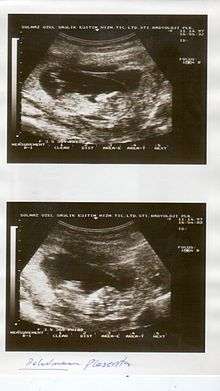

Placental abruption is suspected when a pregnant mother has sudden localized abdominal pain with or without bleeding. The fundus may be monitored because a rising fundus can indicate bleeding. An ultrasound may be used to rule out placenta praevia but is not diagnostic for abruption. The diagnosis is one of exclusion, meaning other possible sources of vaginal bleeding or abdominal pain have to be ruled out in order to diagnose placental abruption.[1] Of note, use of magnetic resonance imaging has been found to be highly sensitive in depicting placental abruption, and may be considered if no ultrasound evidence of placental abruption is present, especially if the diagnosis of placental abruption would change management.[10]